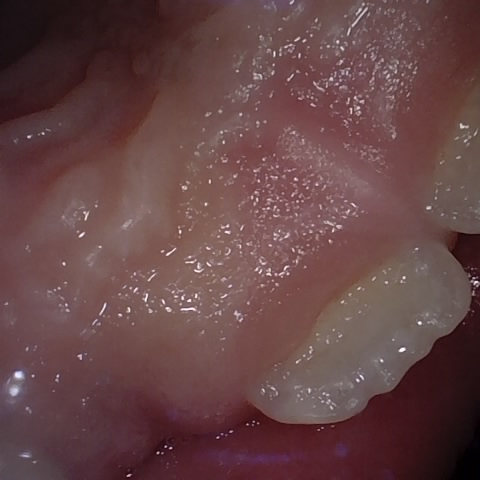

Annotated as "Good"